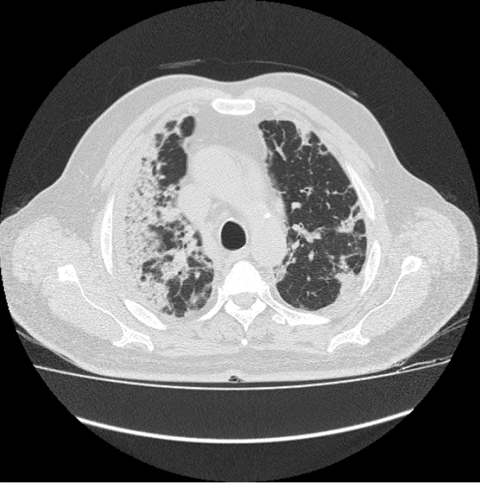

Reticulation as linear consolidation or intralobular density in lungs also reflect the clinical progression of disease in patient's lungs. After GGO and air bronchogram, the presence of reticulation is third most common sign in the patients of COVID-19. It is especially present in the CT images of the patients, which show increasing sensitivity of COVID with time. (Figure 5)

Figure 5 COVID Progression in lungs.

The figure shows rapid increase in the GGO as well as air bronchograms, which shows that with the time COVID is leaving worst impact on the patient’s lungs and thus leading to crazy paving symptoms. This sign is alarming and shows that COVID is going to affect the breathing activities in worst way, if not treated on time. (Figure 6)

Figure 6 Increasing GGO with COVID progression.